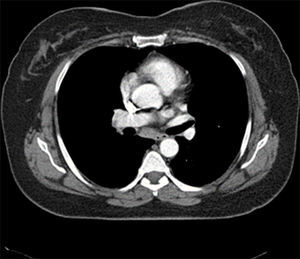

Case report50 years old female patient who was diagnosed with sarcoidosis 10 years ago was admitted to our rheumatology clinic with complaints of fatigue, recurrent fever, dry cough, and arthralgia. During her examination, she described recurrent abdominal pain and fever attacks which occur since her childhood. There is no known feature in her family history and she does not identify FMF in her family. Her medical history revealed that she was examined for a cough and she had a diagnosis of sarcoidosis supported with lymphatic gland biopsy 10 years ago. After 2 years of corticosteroid treatment, her disease restrained, she discontinued to treatment with medication and patient was not present for the subsequent control sessions. Patient's physical examination showed; 38.5°C fever, sensitivity in both ankles and hip joints and negative results for FABER(Flexion, ABduction, External Rotation) and FADIR(Flexion, ADduction, Internal Rotation) tests. In her systemic examination, rough lung sounds were determined during auscultation. There is palpable lymphadenopathy in her right axillar area. In laboratory tests; fasting blood glucose, liver, and renal functions were normal. CBC, thyroid function tests and routine urinalysis were normal. Acute phase reactants were investigated; C-reactive protein (CRP) was 4.03mg/dl (normal 0–0.5mg/dl), and sedimentation rate was 43mm/h (normal 0–20). In serological tests, negative results for RF, ANA, anti-CCP, ANCA, anti-dsDNA was determined. Hepatitis markers (HBV, HCV, HIV) was normal. Serum ACE level was high (87U/L; normal range: 8–52U/L) (Table 1). Her chest X-ray was normal, however, multiple mediastinal and hilar lymph nodes with the greatest dimension of 1cm was identified in her thoracic CT (Fig. 1). Results were consistent with stage 1 sarcoidosis. Regarding the patient's history, the FMF mutation tests were requested. In the FMF gene analysis all M694V, E148Q, R202Q mutations were found in the heterozygous state. After the clinical, radiological, and genetic observation and results of the laboratory test, diagnosis of sarcoidosis with FMF was considered. We made differential diagnosis; lymphoma, infection, other rheumatic diseases (such as connective tissue diseases) were exluded according to investigations. Three times daily oral treatment with NSAIDs and Colchicine 0.5mg tablets was initiated. In her follow-up examination after 3 months, a significant regression in her clinical symptoms was observed and she reported that there are no abdominal pain or fever attacks. Control acute phase reactants were investigated and the levels were determined as normal. Outpatient follow-up is still in progress for the patient with representing overall good condition.